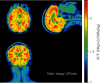

[18F]SynVesT-1 is a PET radiopharmaceutical that binds to the synaptic vesicle protein 2A (SV2A) and serves as a biomarker of synaptic density with widespread clinical research applications in psychiatry and neurodegeneration. The initial goal of this study was to concurrently conduct PET imaging studies with [18F]SynVesT-1 at our laboratories. However, the data in the first two human PET studies had anomalous biodistribution despite the injected product meeting all specifications during the prerelease quality control protocols. Further investigation, including imaging in rats as well as proton and carbon 2D-NMR spectroscopic studies, led to the discovery that a derivative of the precursor had been received from the manufacturer. Hence, we report our investigation and the first-in-human study of [18F]SDM-4MP3, a structural variant of [18F]SynVesT-1, which does not have the requisite characteristics as a PET radiopharmaceutical for imaging SV2A in the central nervous system.